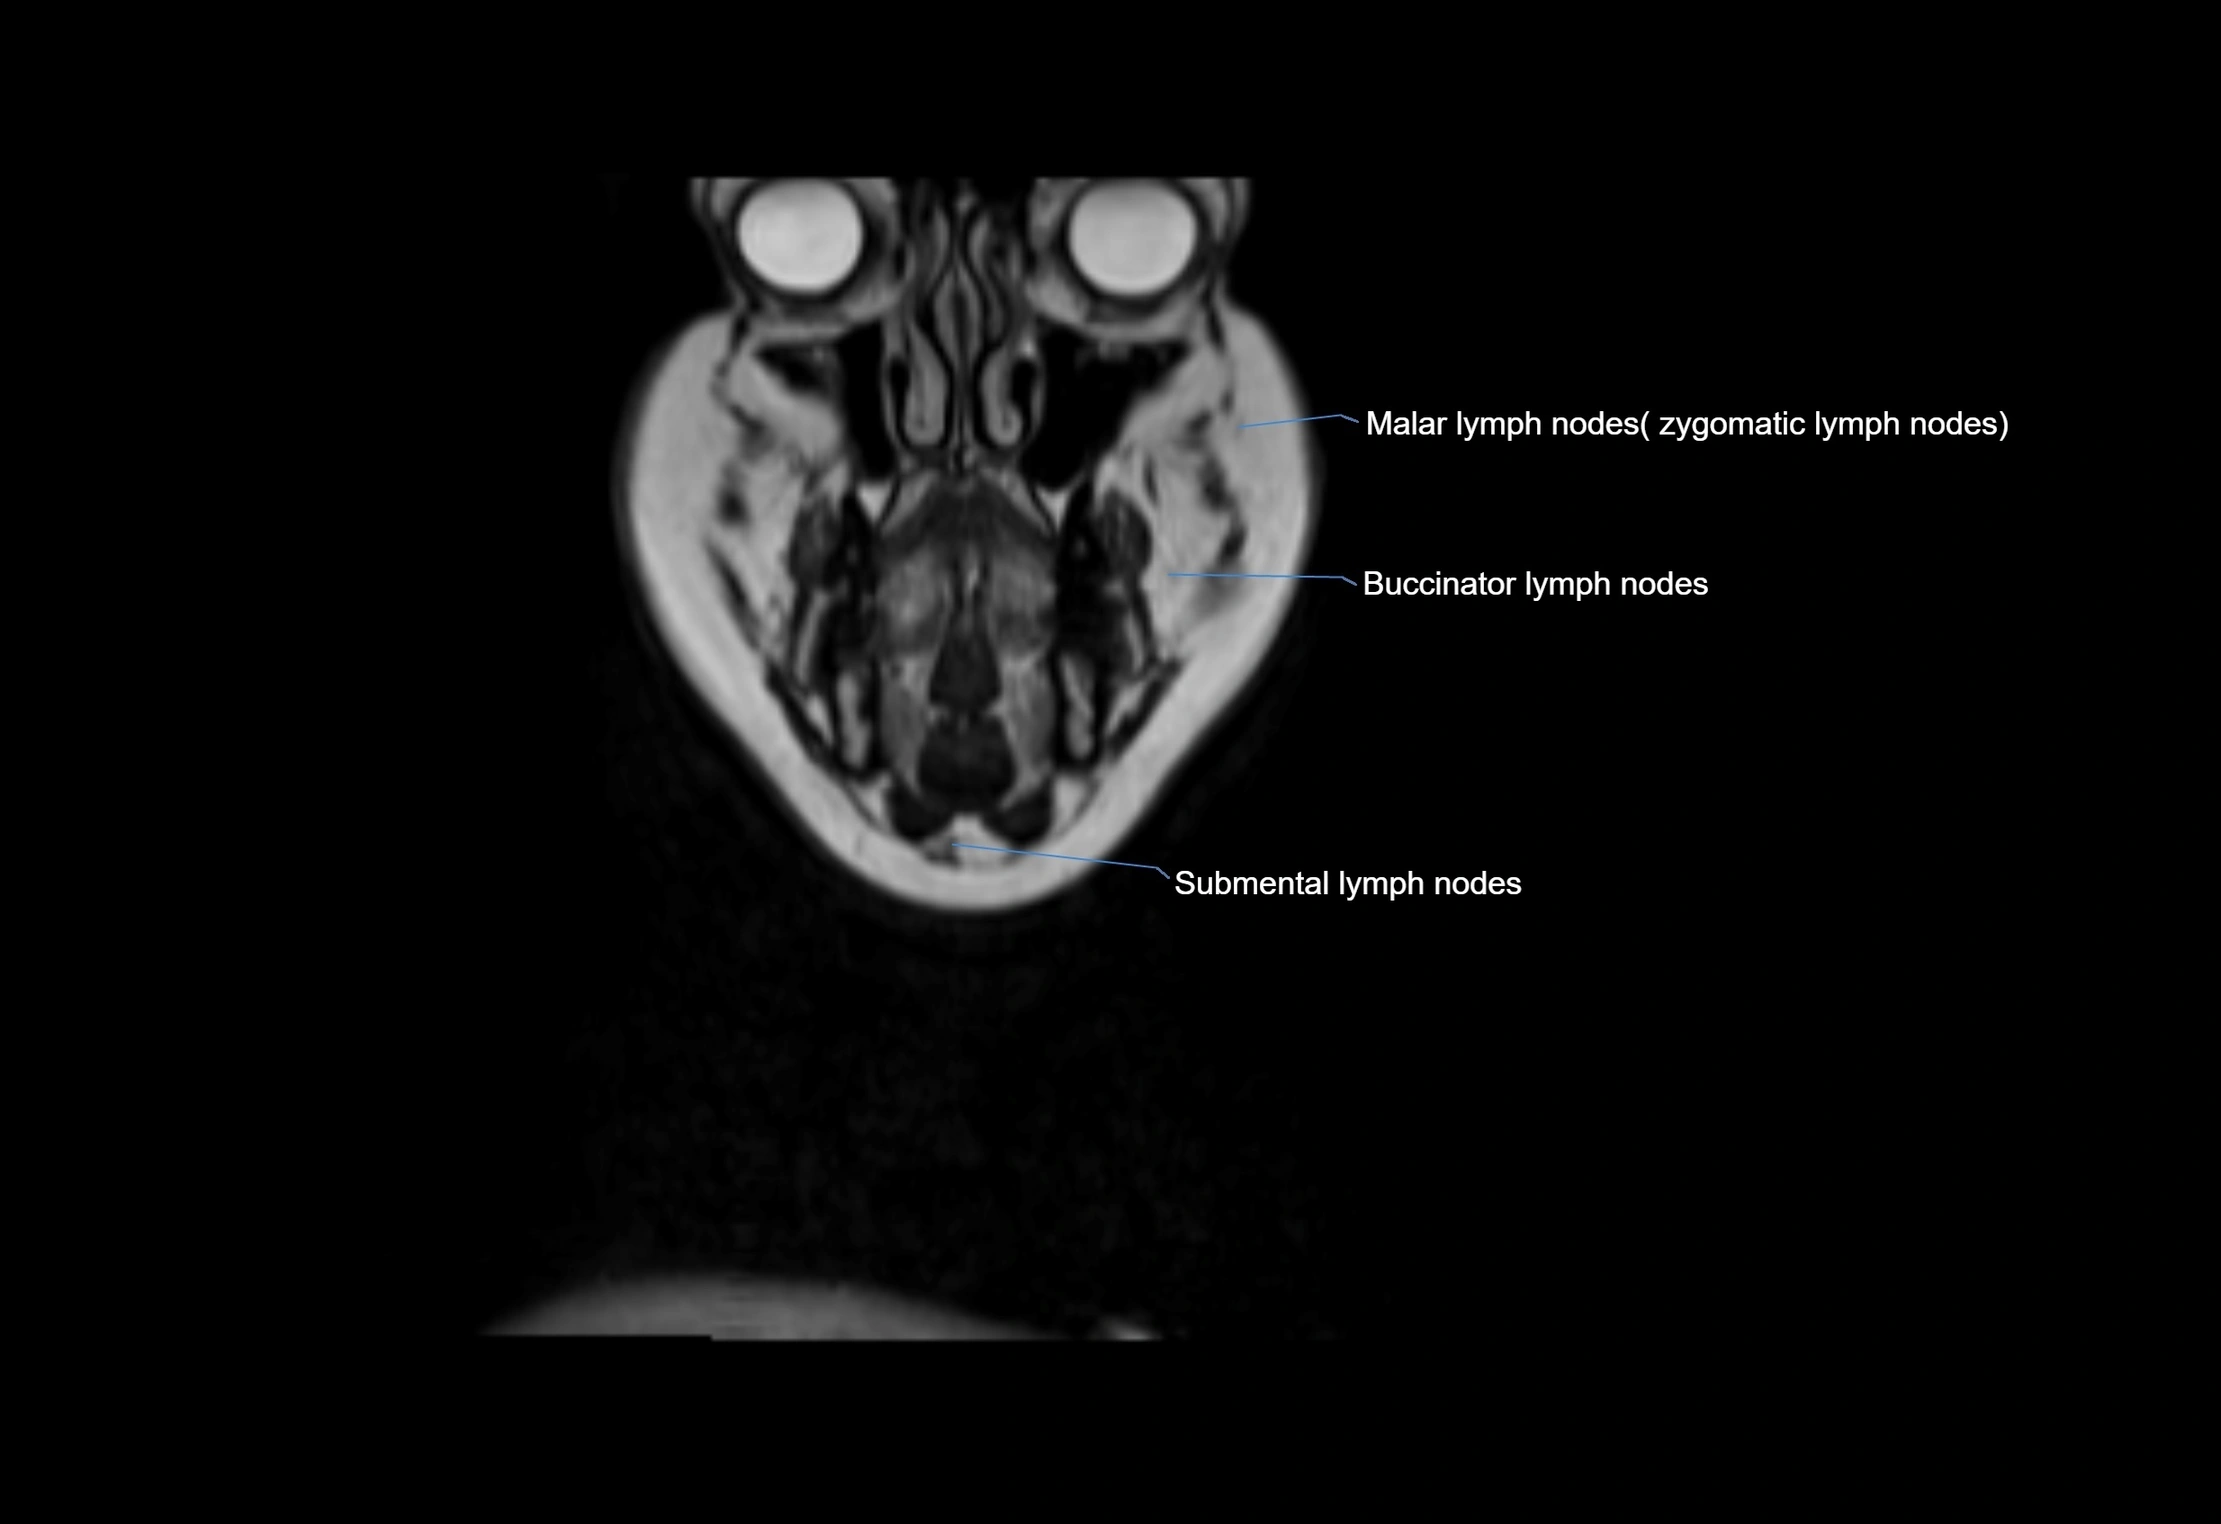

Accessory lymph nodes are small, secondary lymph nodes located along the main facial and cervical lymphatic chains, often adjacent to primary lymph nodes, such as preauricular, submandibular, or occipital nodes. They are typically less than 5 mm in diameter, embedded within subcutaneous fat or connective tissue, and may be variable in number and location. These nodes provide additional filtration and immune surveillance for lymph collected from the face, scalp, and neck regions. Accessory lymph nodes are usually non-palpable in healthy individuals but may enlarge in response to infection, inflammation, or metastasis, making them clinically significant.

Location

• Found along primary lymph node chains, including preauricular, submandibular, parotid, and occipital regions

• Embedded in subcutaneous fat or superficial fascia, often lateral or posterior to primary nodes

• Variable in number; may occur unilaterally or bilaterally, depending on individual anatomy

MRI Appearance

T2-weighted images:

• Nodes show intermediate signal, with surrounding fat bright

• Useful for detecting edema, inflammation, or infiltration

• Fatty hilum may appear slightly hyperintense relative to cortex

MRI images

image